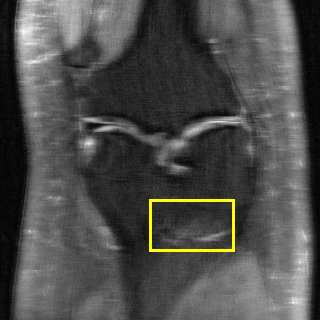

Edge preserving has always been a crucial concern in the design of reconstruction models. To improve the quality of reconstructed images and preserve image edges, some works suggested introducing edge priors in the original restoration problem to preserve image edges [4, 34]. However, they will suffer from complicated algorithm design and time-consuming training processes. Recently, some more efficient methods have been proposed to use edge maps as external guidance for image restoration. For example, Yang et al. [48] used off-the-shelf edge detectors to extract image edges from the degraded images. Fang et al. [12] predicted image edges by constructing an edge reconstruction network. Huang et al. [18] designed a novel dual discriminator GAN framework for solving fast multi-channel MRI, in which one GAN network is built for edge information enhancement. Inspired by these methods, we also consider introducing image edge prior as external guidance to MRI reconstruction since 1) image edges are prominent and distinguishable features in MRI (see Fig. 1), which can serve as a good guide to the model to recover high-frequency details; 2) the ground truth edges can be easily fetched via ordinary edge extraction operators, like Canny, Sobel, and Prewitt, which means that the edge maps can be learned in a data-driven manner. However, how to effectively utilize image edge priors to guide image reconstruction still remains a challenge. In some methods, edge information was simply concatenated with the input image and passed to the next stages. Though this is a simple way to utilize the edge priors, it may not give full play to the guiding role of the edge priors. Therefore, in this work, we want to explore a more efficient and effective mechanism to fully take advantage of image edge priors.

(a)

(b)

(c)

fastMRI is a large-scale MR dataset jointly established by Facebook AI Research and NYU Langone Health. It provides both knee and brain datasets for evaluation. In our work, we use the multi-coil knee dataset, which was acquired on three clinical 3T systems or one clinical 1.5T system using a 15-channel knee coil array. The dataset includes data from two pulse sequences, yielding coronal proton-density weighting with (PDFS) and without (PD) fat suppression. As is shown in Fig. 1, PD images usually contain more structural and prominent edge features than PDFS images, which suggests that it is more challenging to use edge guidance on PDFS datasets. Therefore, we explore the effectiveness of EAMRI on these two modalities. Following [13], for both PD and PDFS knee datasets, we separately filter out 227 volumes (8332 slices) for training and 24 volumes (1665 slices) for testing. The dataset is centrally cropped to .